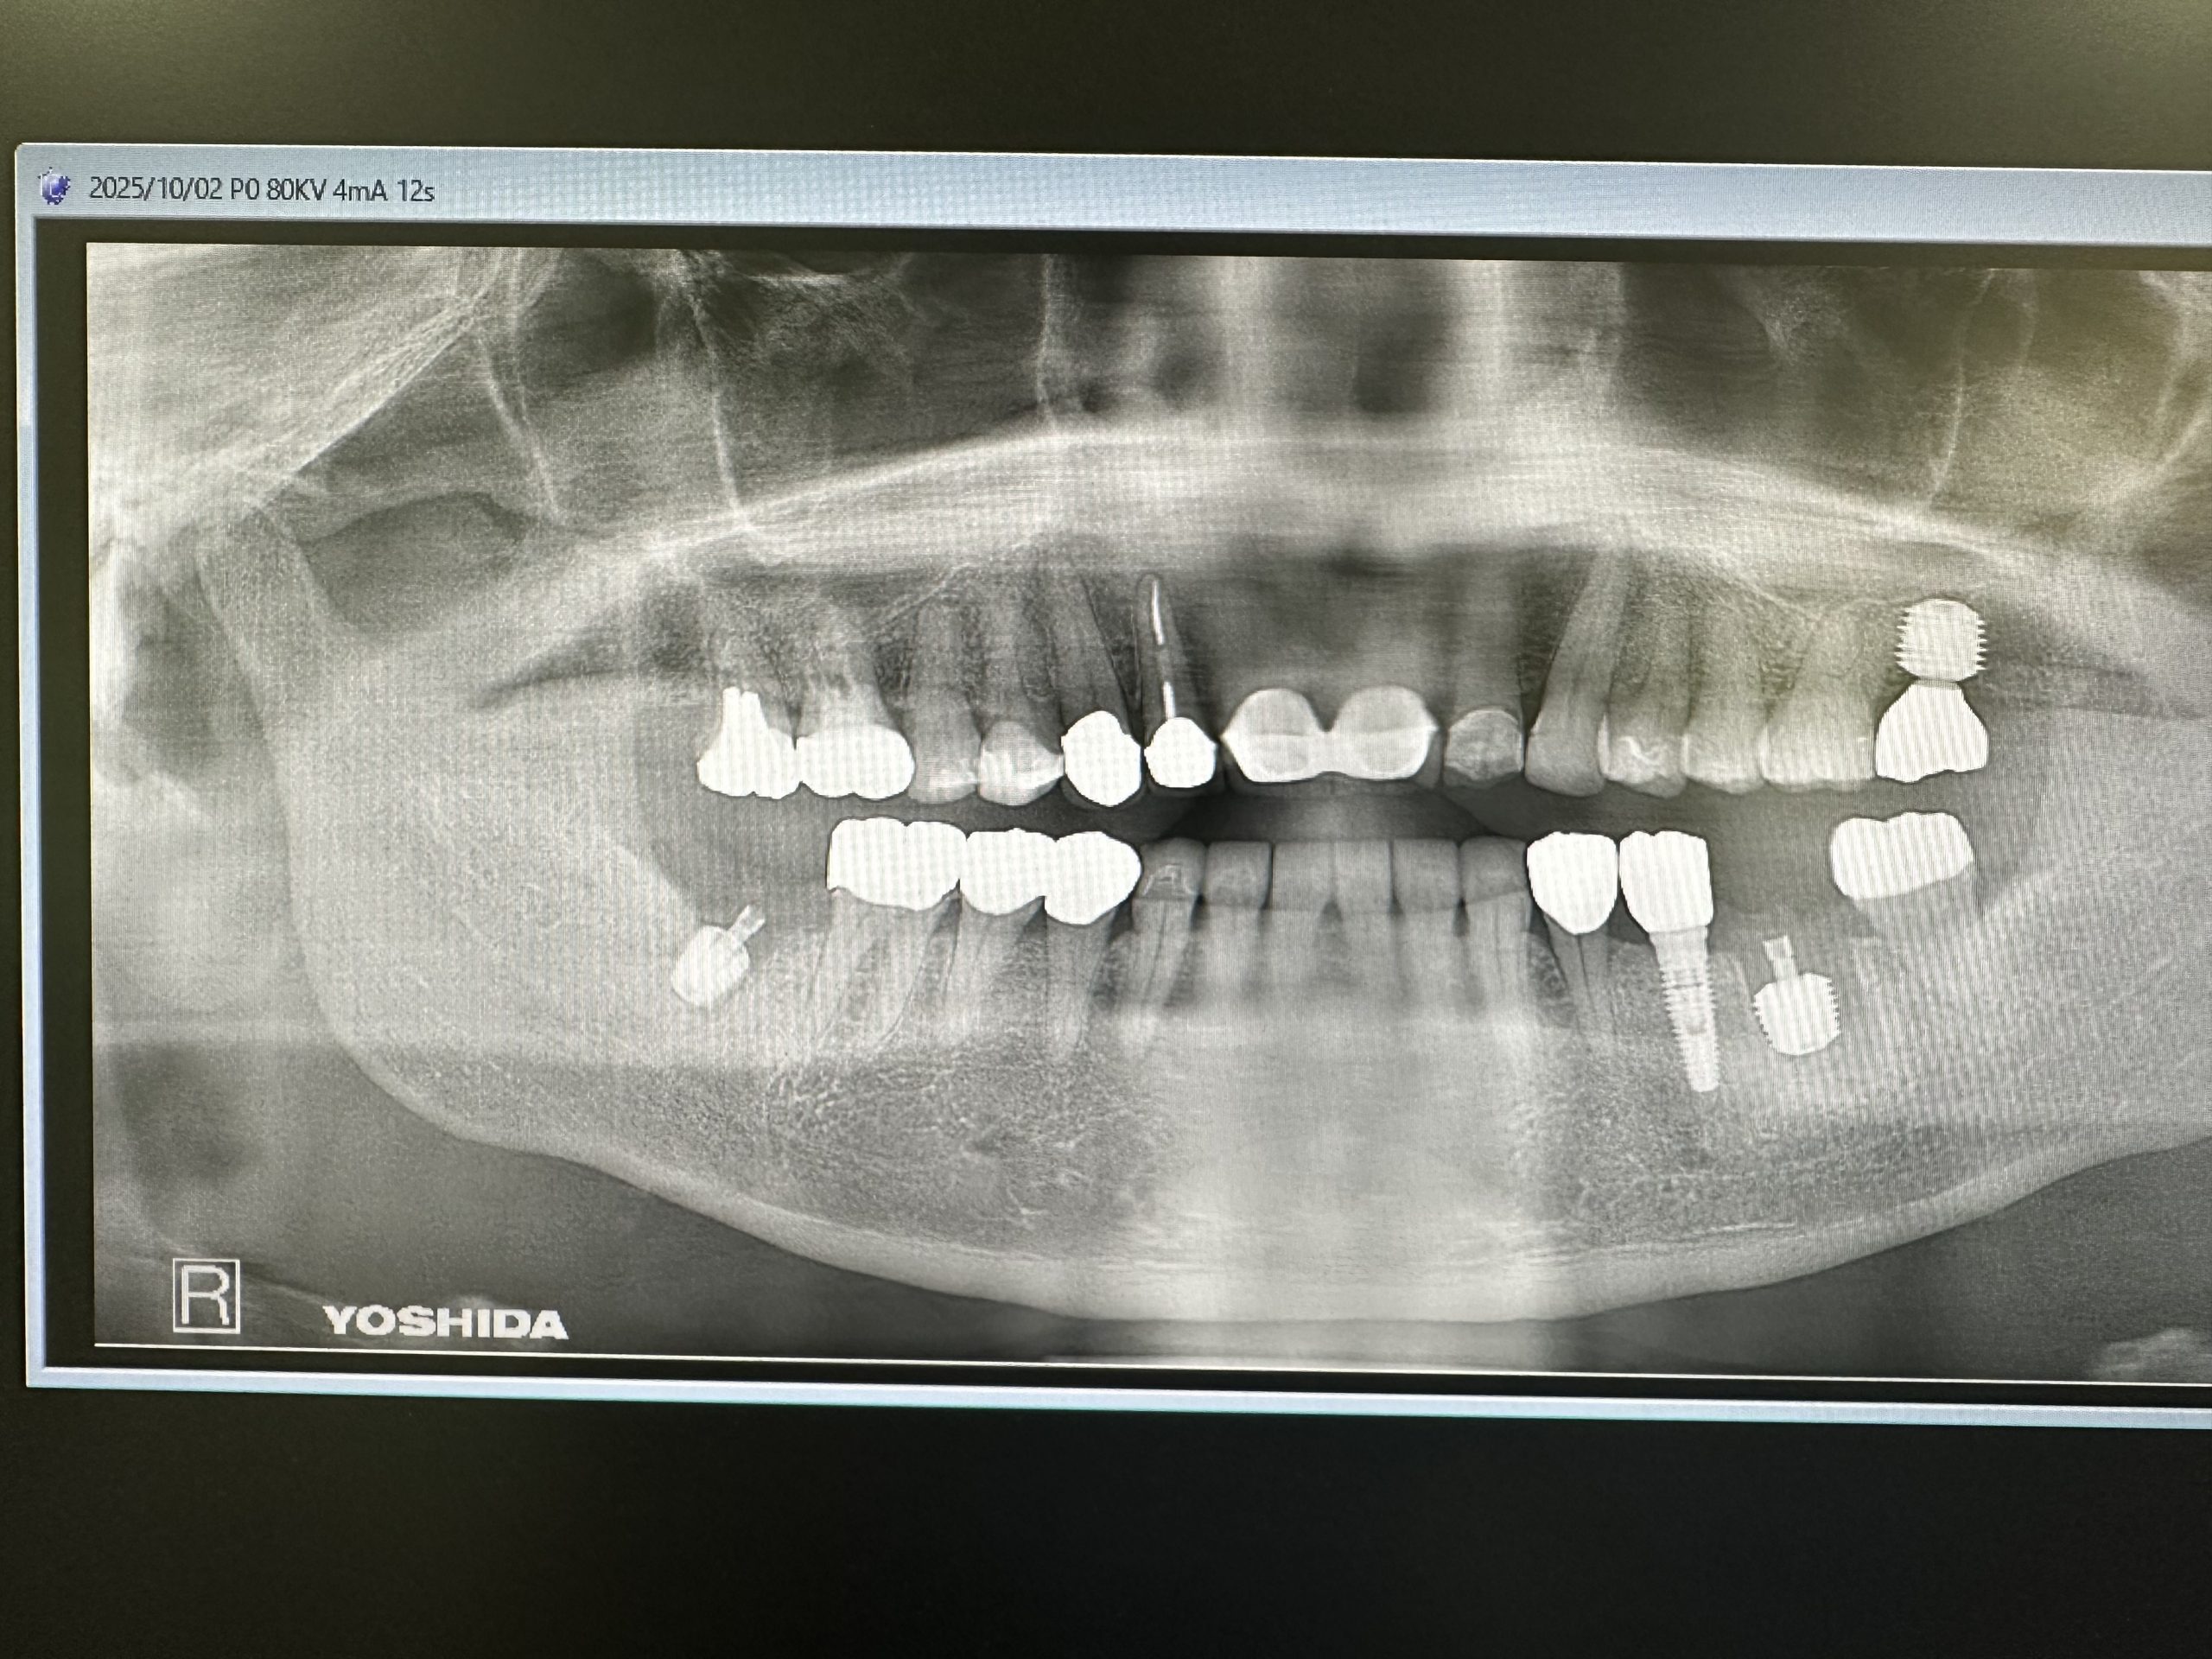

本日は午前、午後とインプラントオペあり

午後は40分で終わり

集中MAX、セプトカイン使用したが奏功しづらかった💦キシロカイよりは断然効くけど